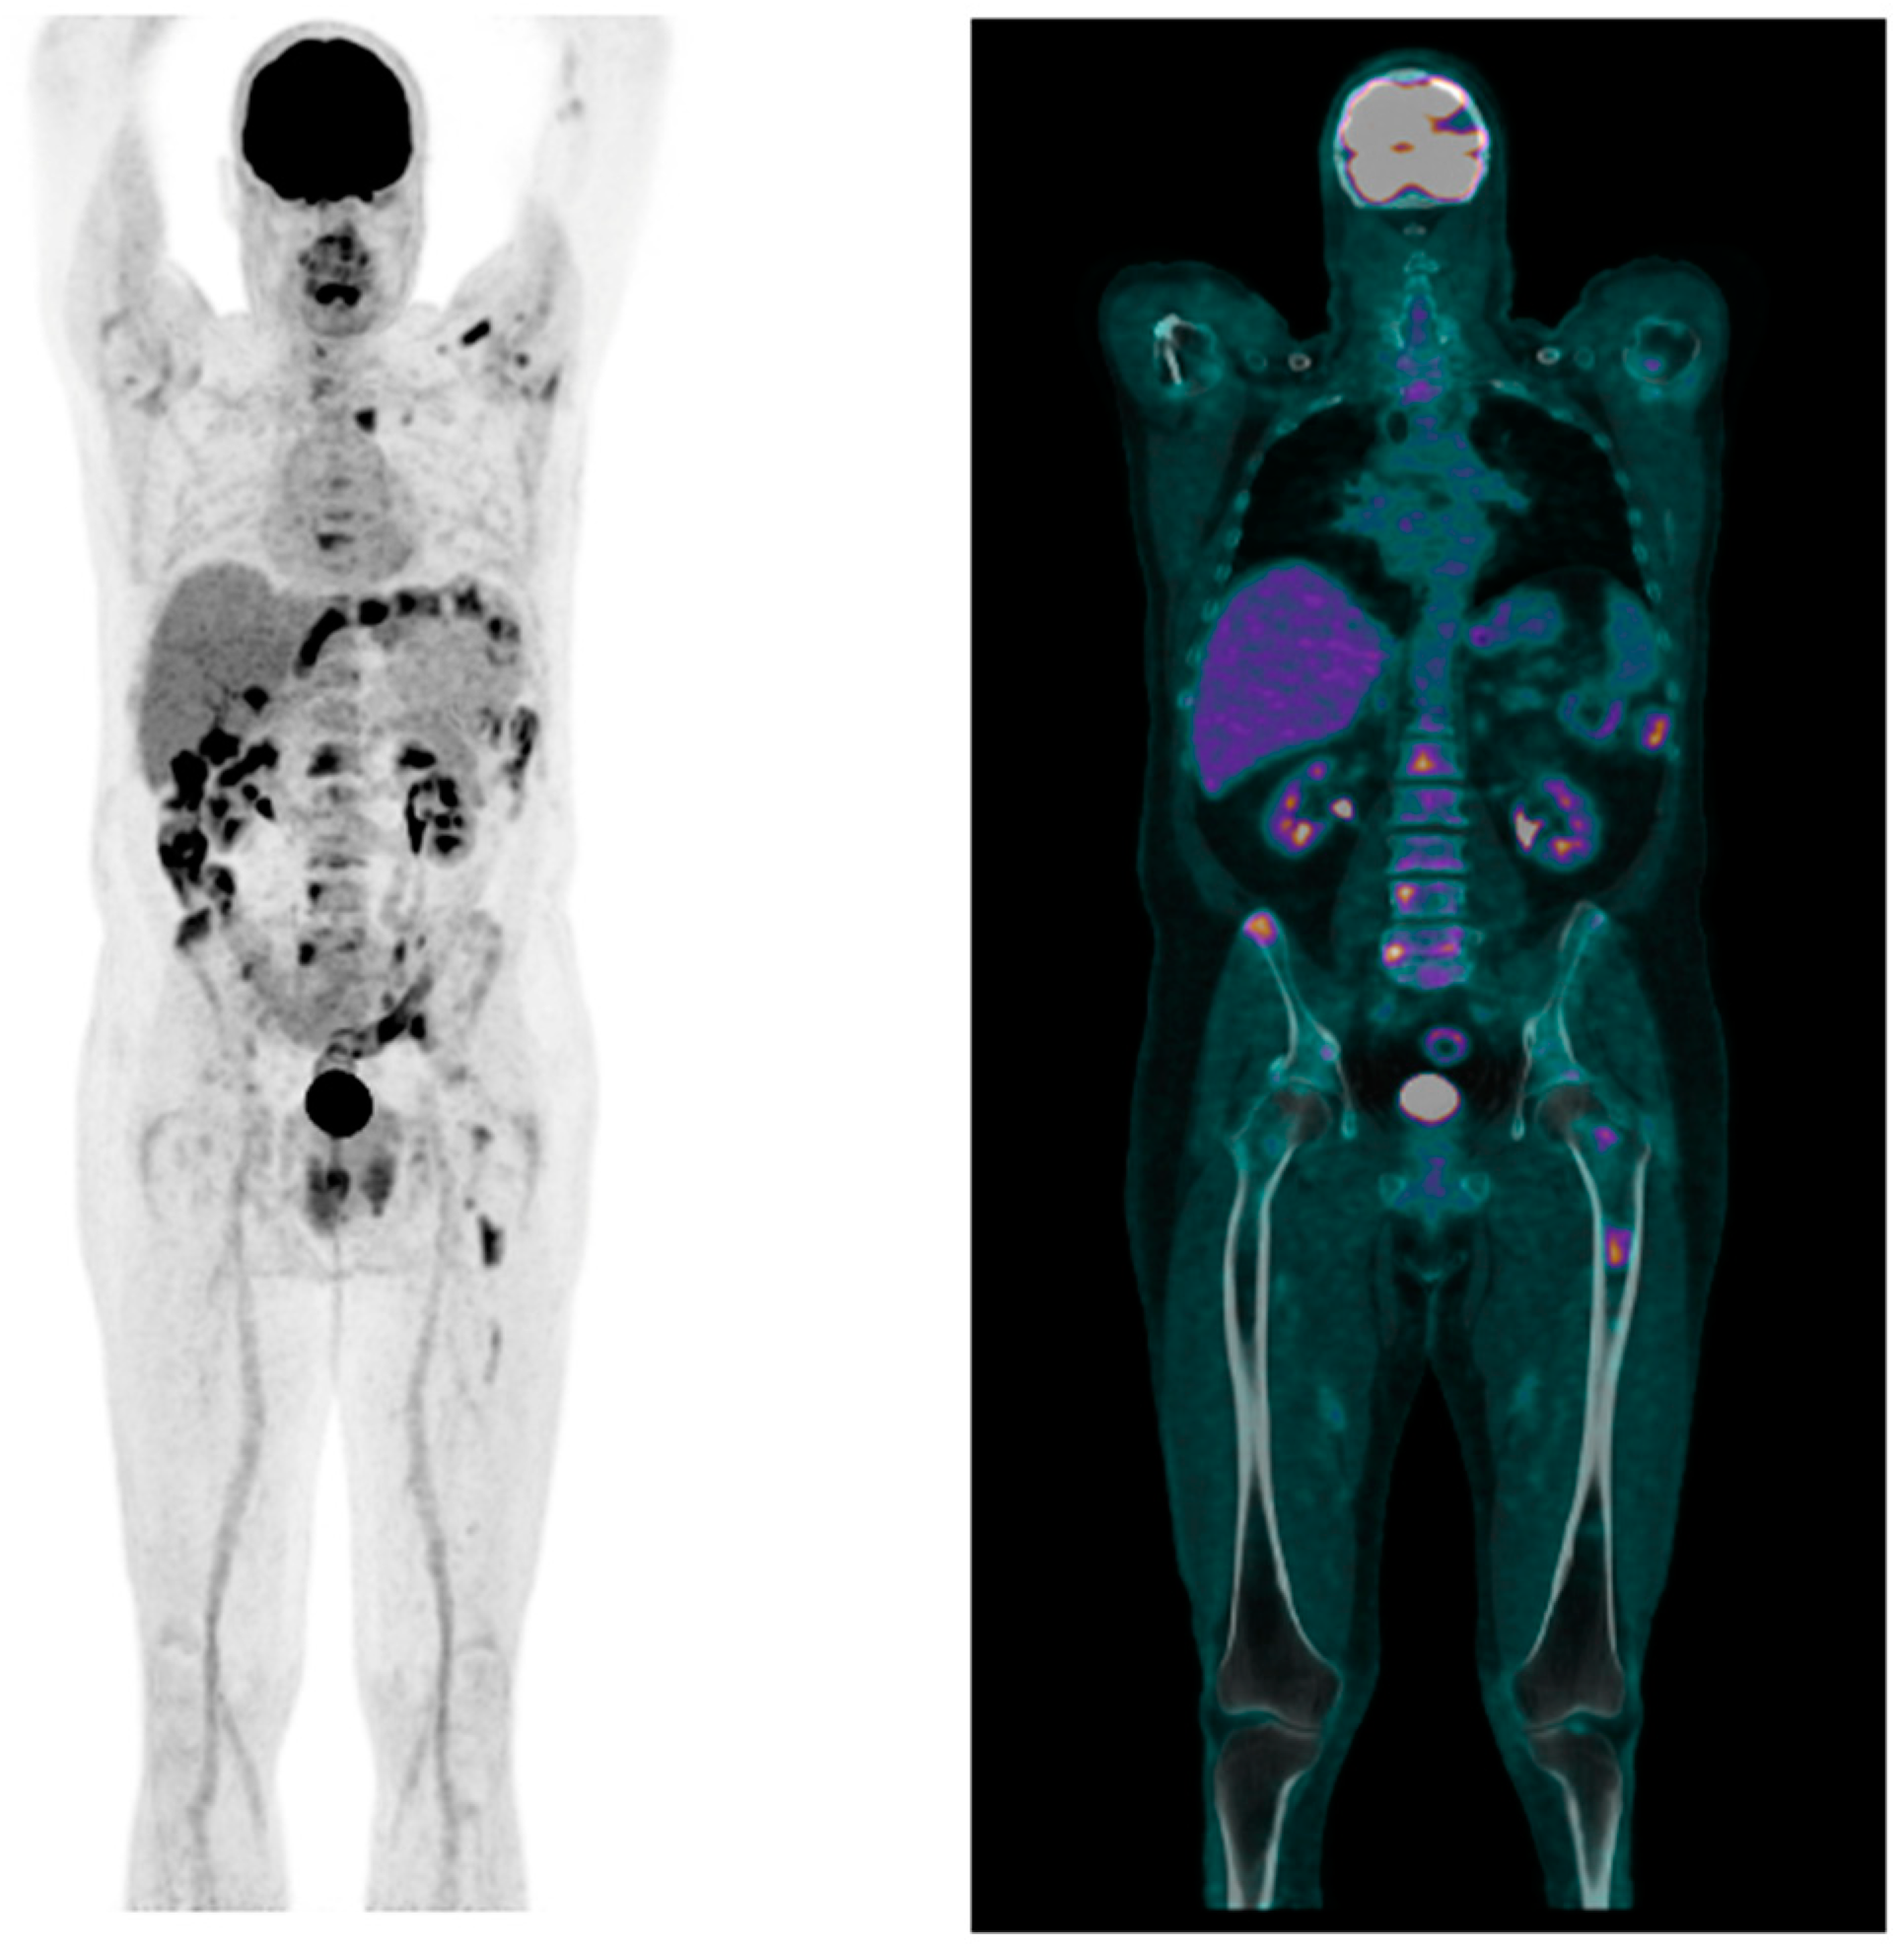

A Rare Case of Primary Bone Follicular Lymphoma with Multiple Osteolytic Lesions: A Case Report and Review of the Literature

Togni, C.; La Verde, G.; Pelliccia, S.; Bianchi, M.P.; Di Napoli, A.; Lanzolla, T.; Zerunian, M.; Laghi, A.; Maiorana, G.; Taglietti, A.; et al. A Rare Case of Primary Bone Follicular Lymphoma with Multiple Osteolytic Lesions: A Case Report and Review of the Literature. Hemato 2024, 5, 388-395. https://doi.org/10.3390/hemato5040028